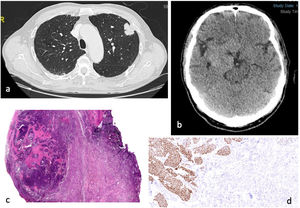

(a) Thorax CT axial contrast-enhanced: 33mg lung spiculated mass located in the upper left lobe contacting and thickening the visceral pleura (T2a). (b) Cranial CT axial, unenhanced: large right-sided extra-axial mass of 55mm, hyperdense, compressing right cerebral peduncule and closely related to arterial vascular structures. (c) HE stain 10×; poorly delimited basaloid cell nodule with areas of necrosis over a proliferation of spindle cells corresponding to meningioma (squamous carcinoma). (d) Immunohistochemistry P40 100×; epithelial cells from squamous carcinoma show P40 nuclear positivity while spindle meningeal cells are p40 negative.

A craniectomy with lesion excision was done in November 2022, and pathology reported squamous lung cell metastasis inside a meningioma tumour (Fig. 1c and d).